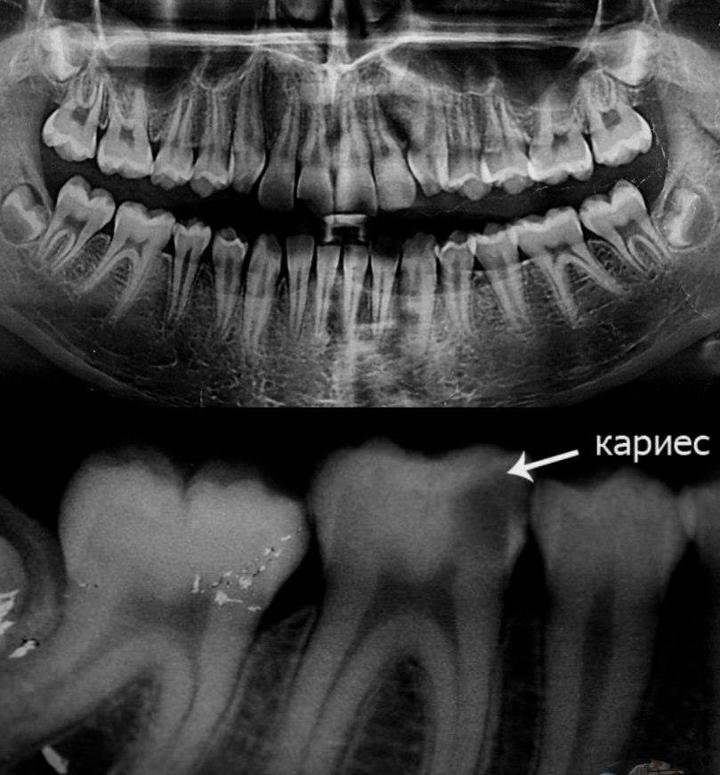

Дентальные снимки и диагностика кариеса